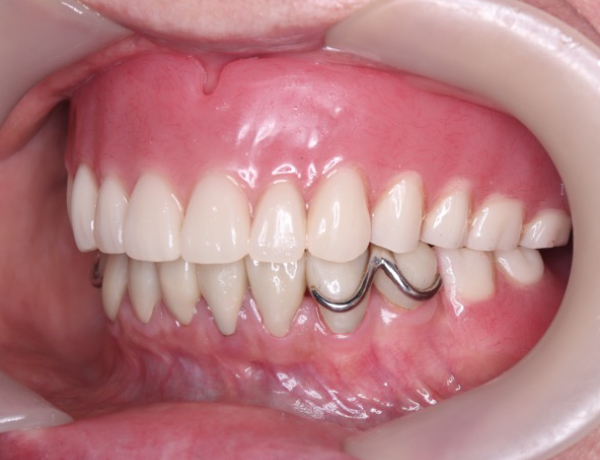

正面観

左下に入れ歯が入っておらず歯がないので、噛み合わせは左右アンバランスになってますね。赤丸の部分は、骨隆起ですね!噛み合わせの強い方に現れる骨の隆起になります。

下あご

下の入れ歯も良く折れたり壊れたりしてしまうとのことでしたので、細い部分や力のかかる部分は、金属にしました。金属にした場合に、骨隆起が多い患者さんは、入れ歯めり込んだりして、痛みの原因になりかねないので、注意が必要です。

下骨隆起の部分を上手く避けて作製されているのが分かると思います。普通の金属の入れ歯ですと覆うのですが、それだと分厚くなり過ぎてしまうので、上手く骨隆起を避けて作製しています。

左右のかみ合わせも非常にバランス良く噛ませています。また、バネの部分を上の歯が噛み込まないように工夫をしています。良くこのバネの部分で折れてしまう場合がありますので、それを考慮してあります。